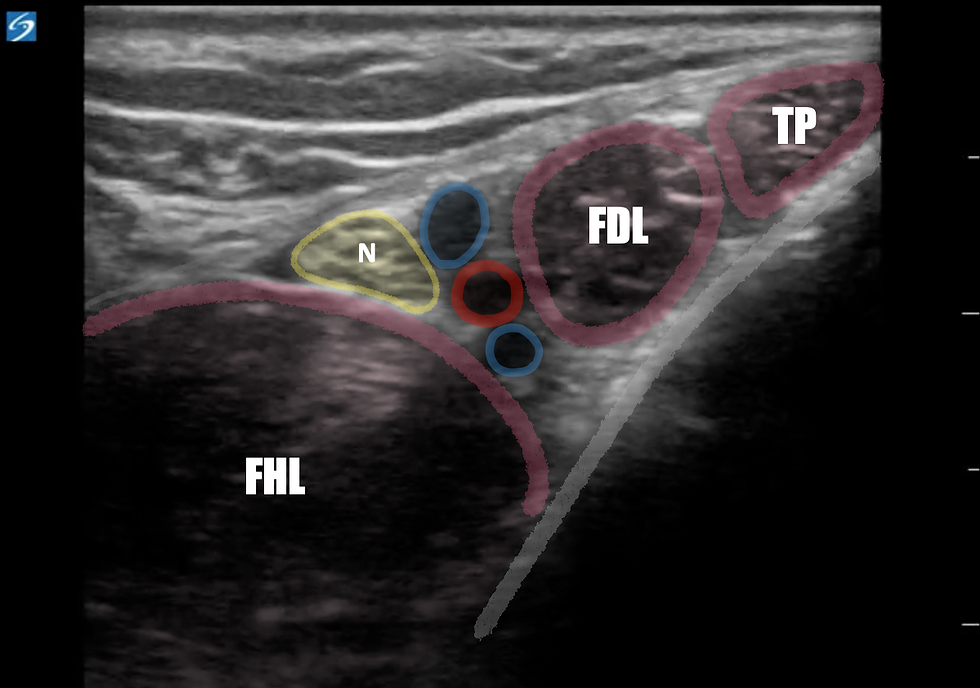

Figure 7: Ultrasound appearance at location of block. (FHL=Flexor Hallucis Longus mm., N=Posterior tibial nerve, Red circle= posterior tibial artery FDL=Flexor digitorum longus tendon, TP=tibialis posterior tendon)